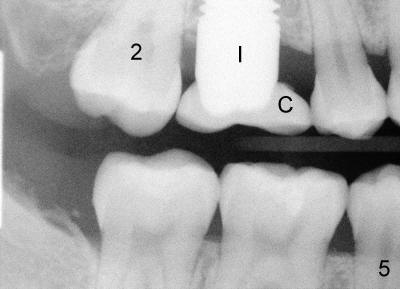

After crown cementation, the patient moves to Washington DC. She returns on vacation to replace PFM crown (Fig.4 C) with chip (*). Fig.5 shows a new Emax crown (C) after cementation. What is the most troubling is that there is cracking sound during cementation. The patient calls from DC, reporting that there is minor chipping. It is planned to fabricate a Zirconia crown next time she returns for visit in Atlanta.